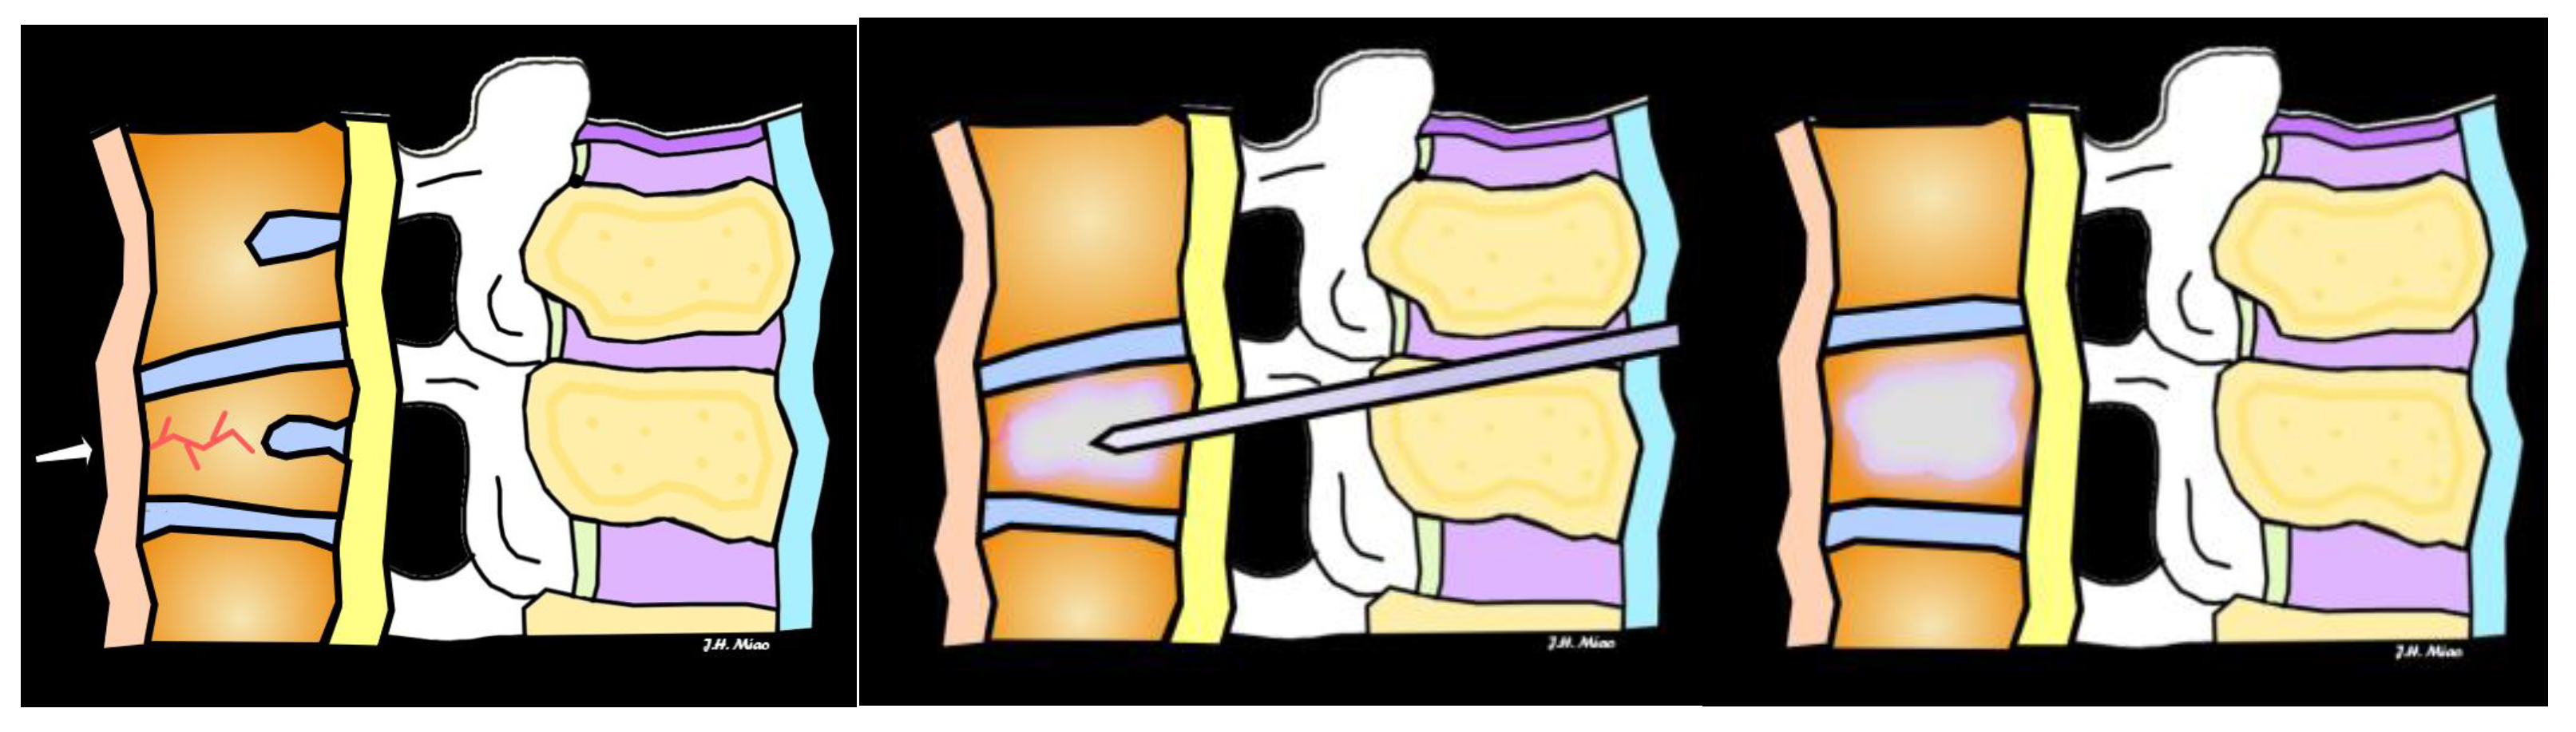

6. Treatment and Management

| Vertebroplasty | Injection of bone cement into fractured vertebra to stabilize | Painful fractures not responding to conservative treatment, no neurological symptoms | Provides rapid pain relief, improves vertebral stability |

| Kyphoplasty | Balloon inserted to restore vertebral height, followed by cement injection | Fractures causing significant vertebral height loss, pain, or deformity | Restores vertebral height, reduces pain, improves mobility |